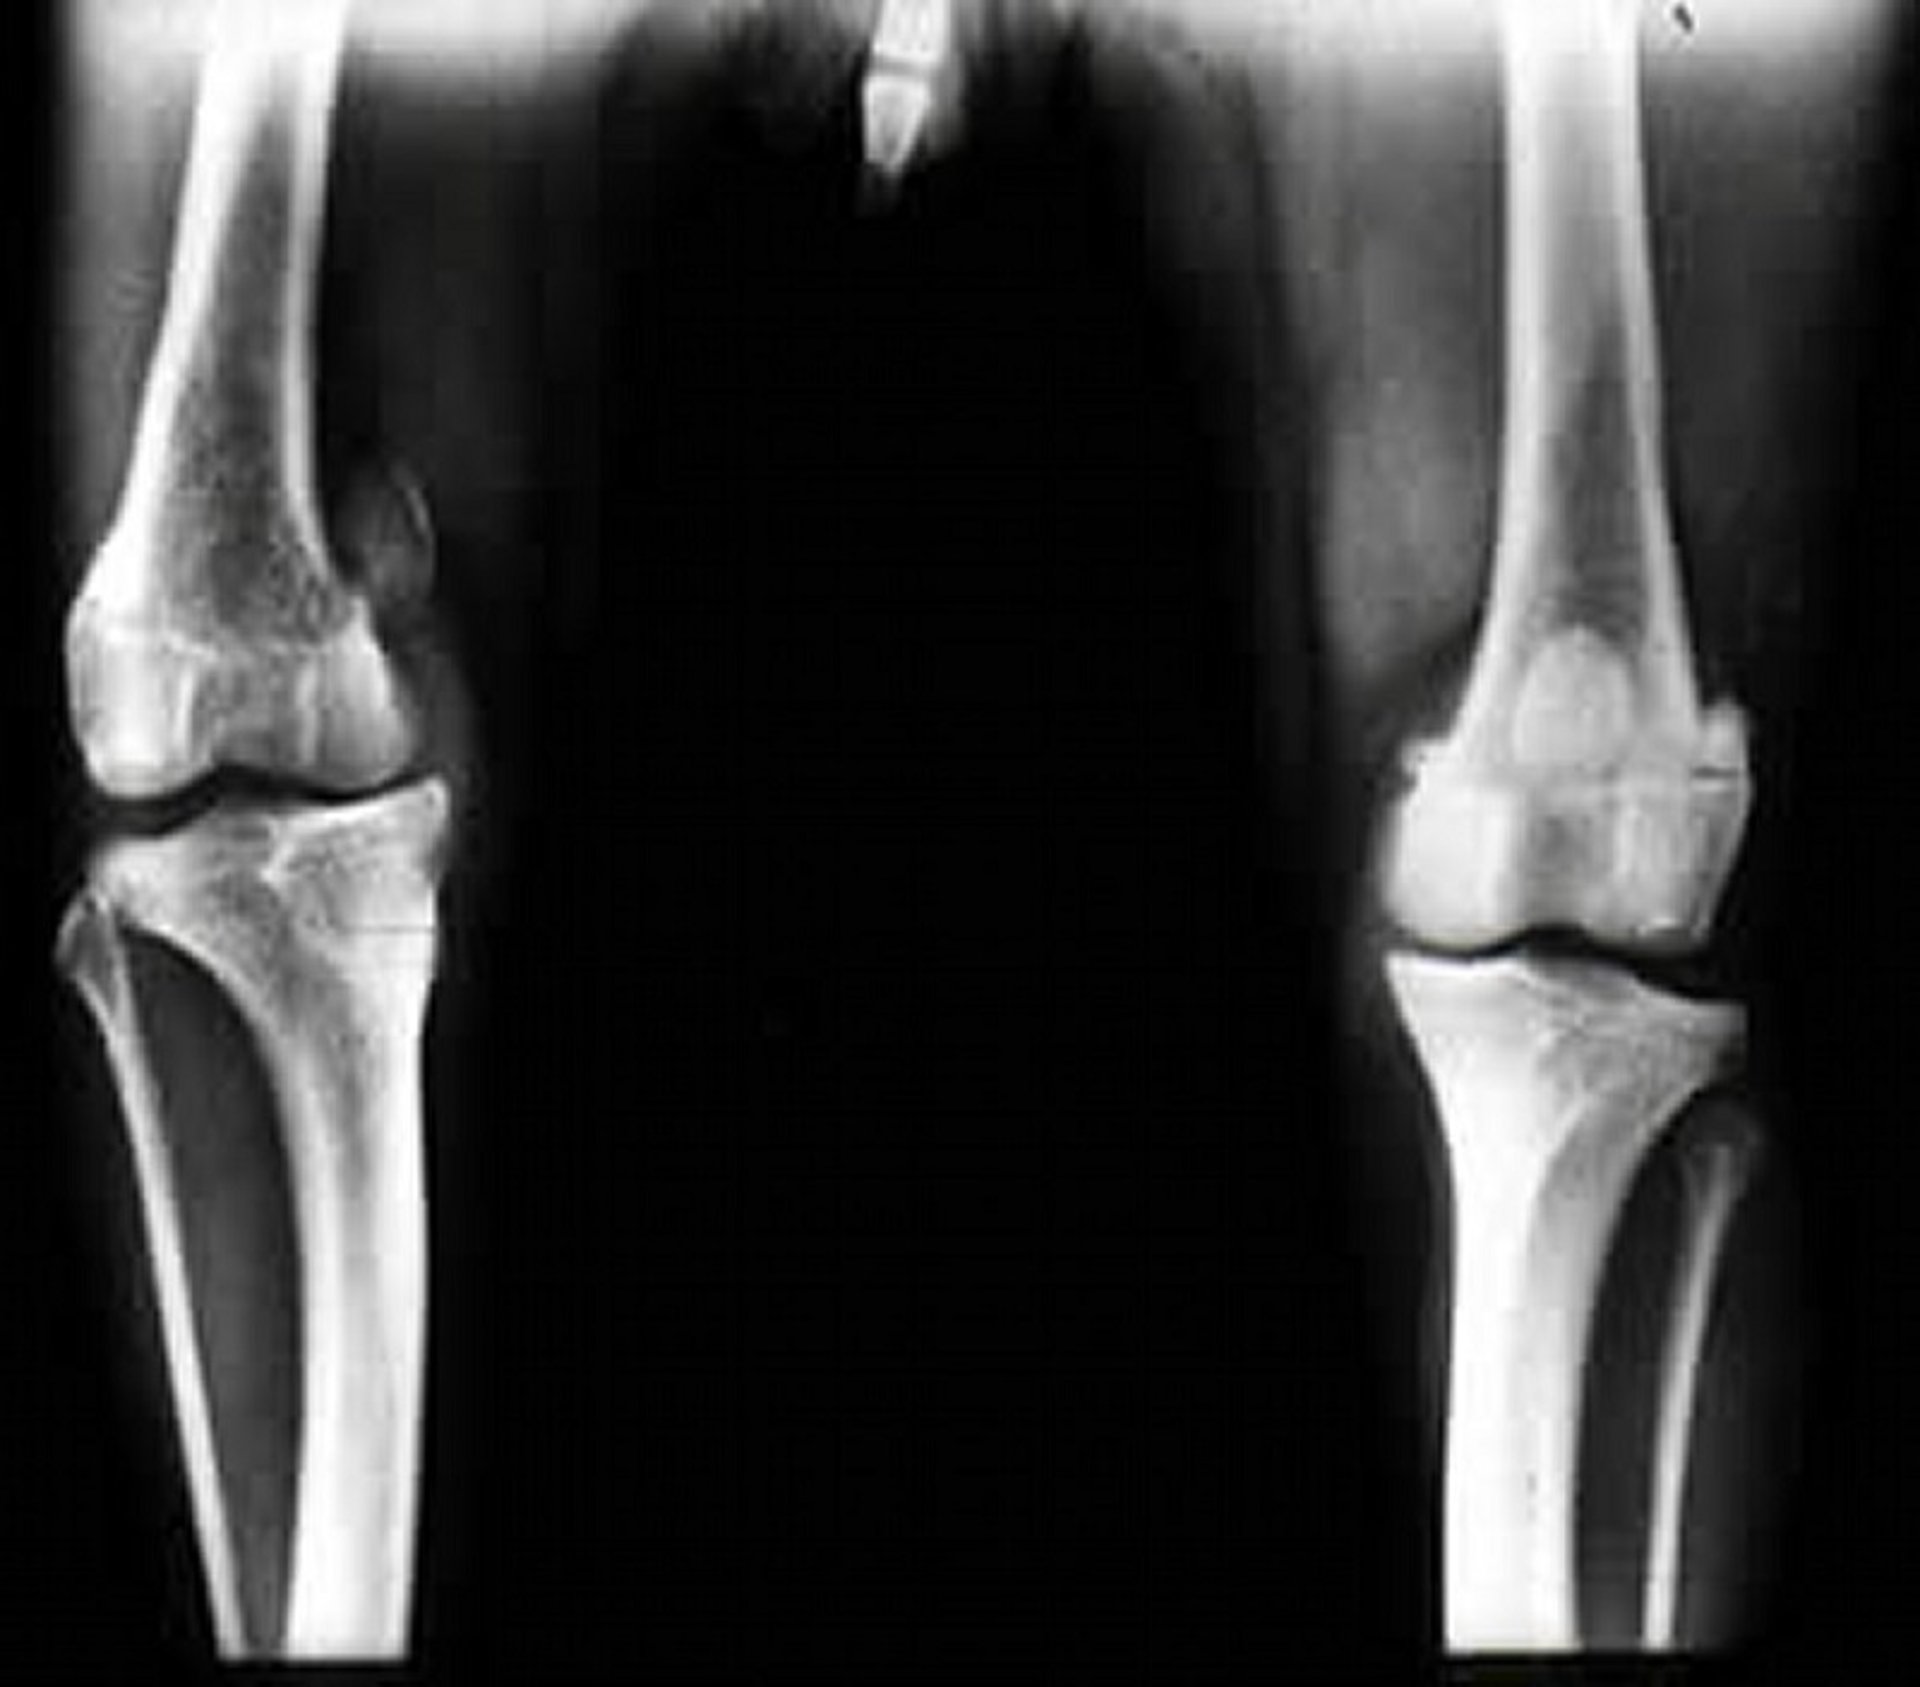

Radiography of dogs and cats with patellar luxation reveals various degrees of limb changes based on the direction and grade of the luxation.

With medial patellar luxation, possible radiographic findings include distal femoral varus, femoral rotational deformity, medial displacement of the tibial tuberosity, and medial rotation of the tibia (see ).

Craniocaudal radiographic view of the stifle joints of a dog with right-sided medial patellar luxation. Note the displacement of the patella and internal rotation of the tibia, with increased medial soft tissue fibrosis.

Courtesy of Dr. Ronald Green.